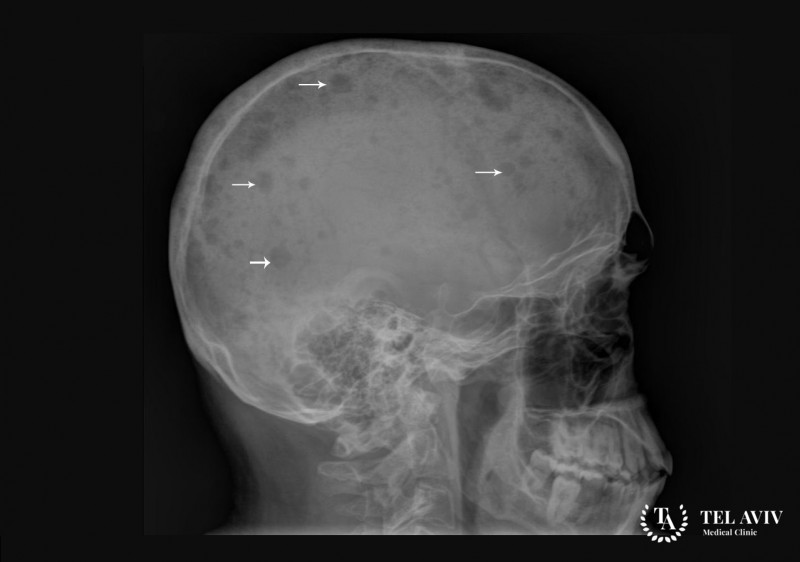

- рентген костной ткани;